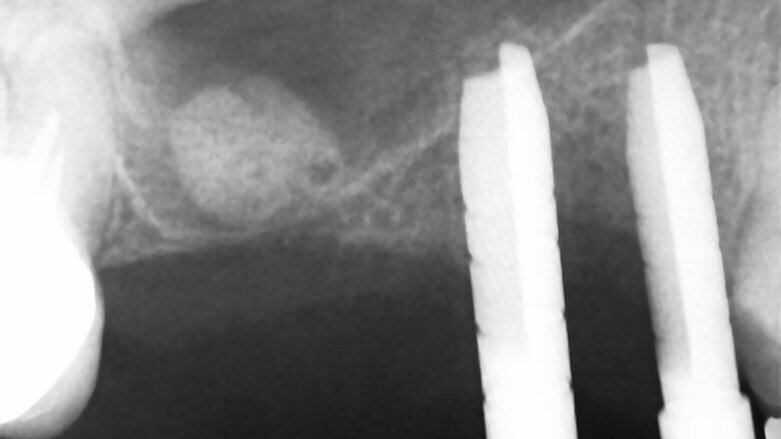

Na naše pracoviště se dostavil dvaapadesátiletý pacient s žádostí o estetickou a funkční rekonstrukci chrupu. Osobní anamnéza byla ze stomatologického pohledu nevýznamná a z anesteziologického hlediska byl pacient klasifikován jako ASA I (zcela zdravý jedinec). Před zahájením ošetření pacient podepsal informovaný souhlas. Na základě radiologického (obr. 1a–e) a klinického (obr. 2a) vyšetření jsme navrhli zavedení implantátů do distálního úseku prvního kvadrantu k náhradě zubů 14, 15 a 16.

Preoperační CT analýza: a) koronální řez zachycující omezenou nabídku vertikální kosti a b) panoramatický pohled na horní čelist se zjevným nedostatkem vertikální reziduální kosti v prvním kvadrantu. c–e) Sagitální řez v oblasti zubu 16 s vertikální nabídkou kosti menší než 1 mm.